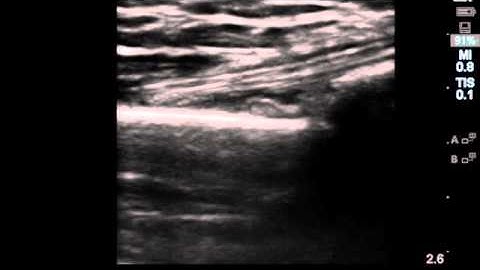

Ultrasound Guidance in the Reduction of Closed Distal Radius Fractures